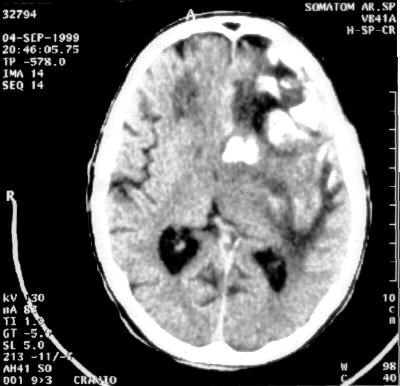

Rottura dell’intima, rottura della seconda membrana dell’arteria cerebrale media, emorragia in atto, devastazione di ampia area cerebrale a sinistra, mesencefalo e acquedotto di Silvio inondati, dislocazione della linea mediana, shift grave; stato di coma, soggetto femmina, 39 anni, perduto. Feto in imminente pericolo di vita. Necessaria estrazione entro un’ora al massimo.

Stato di coma areflessico, pupille midriatiche media ampiezza non reagenti, attività respiratoria spontanea assente o insufficiente, GCS 3. Paziente decerebrata. Imminente pericolo di vita.